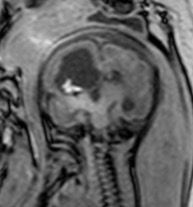

imagerie

- l’échographie, couplée au Doppler est l’examen de référence, non invasif, fait au lit du patient et répétable, il permet de diagnostiquer des lésions cérébrales associées et de suivre l’évolution de la taille ventriculaire et du retentissement hémodynamique

Echo-Doppler montrant une HTIC sévère avec reverse-flow (à gauche), et correction hémodynamique après ponction soustractrice (à droite) - l’IRM est importante à visée pronostique